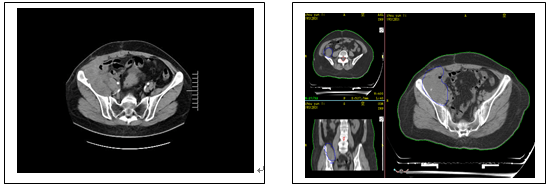

下圖為2021年8月復(fù)查MR